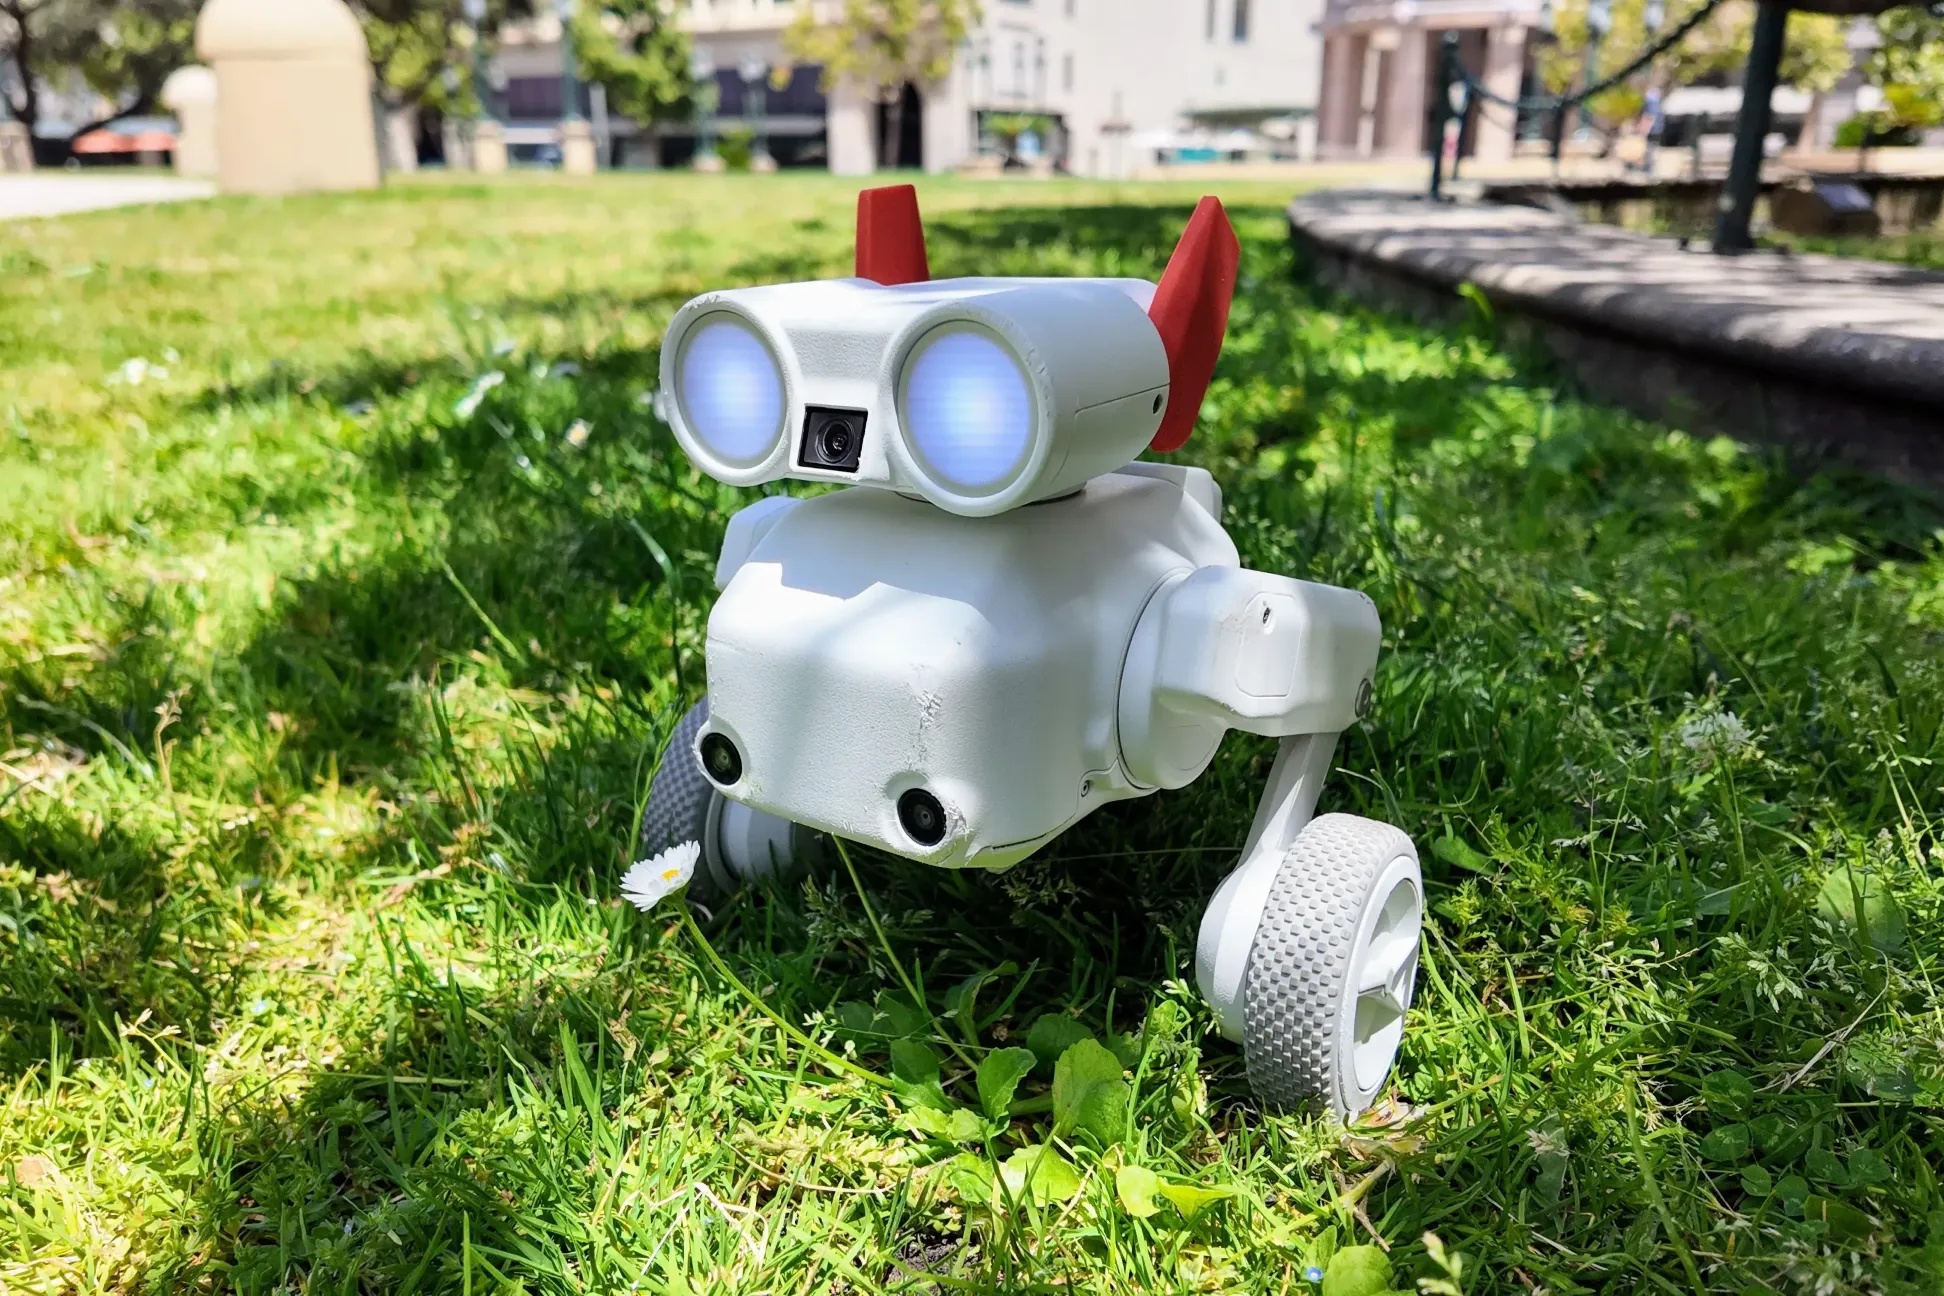

تشخیص خونریزیهای مغزی در مدالیته با هوش مصنوعی

دکتر محمد افشاری، فارغالتحصیل دانشگاه علوم پزشکی کاشان و سرپرست تیم تحقیقاتی، در گفتوگو با خبرنگار آنا اعلام کرد: این سیستم با پردازش ۳۰ هزار تصویر سیتیاسکن (معادل دادههای ۵ هزار بیمار) اجرا شده و قادر است تصاویر نرمال و غیرنرمال را با دقت بالا تشخیص دهد.

هدف اولیه پروژه، تشخیص سکتههای مغزی هموروژیک بود، اما قابلیت گسترش به بیماریهای دیگر مانند آلزایمر و ام اس نیز وجود دارد. کاهش زمان تحلیل تصاویر توسط پزشکان و جلوگیری از خطاهای انسانی از مزایای کلیدی این روش است.

استفاده از این فناوری در کشور میتواند سرعت تشخیص بیماریها را به شکل چشمگیری افزایش و هزینههای درمانی را با تشخیص زودهنگام کاهش دهد.همچنین استفاده از این روش می تواند انقلابی در نظام سلامت باشد و دسترسی به خدمات تشخیصی پیشرفته را در مناطق محروم فراهم کند.

افشاری تأکید کرد در صورت دریافت حمایتهای لازم، این سیستم میتواند ظرف ۱ تا ۲ سال به مرحله عملیاتی و استفاده در بیمارستانها برسد. وی خواستار همکاری فوری مسئولان برای حفظ جایگاه پیشروی ایران در این حوزه شد.

این دستاورد، گامی کلیدی در تحول پزشکی با هوش مصنوعی است که نهتنها جان بیماران را نجات میدهد، بلکه ایران را به عنوان پیشگام در فناوریهای تشخیصی جهان مطرح میکند.

این فناوری که تاکنون در کشورهای پیشرفتی مانند آمریکا و اروپا توسعه یافته، در رویداد سالانه هوش مصنوعی پارک پردیس رتبه کسب کرده است.